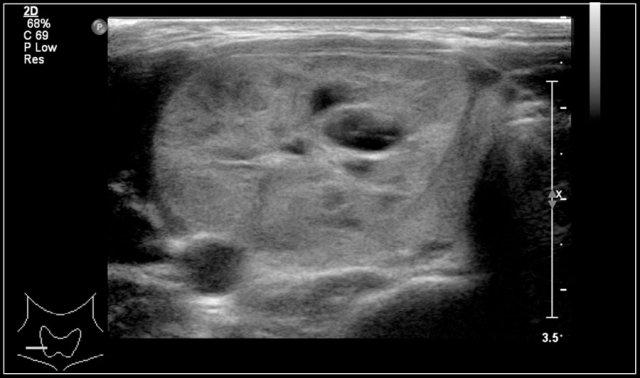

Video cho thấy một khối sưng xuất hiện qua đêm ở một bé gái 13 tuổi.

Một tổn thương giảm âm được nhìn thấy nằm nông so với động mạch cảnh và sâu so với cơ ức đòn chũm.

Không thấy sự di chuyển của nội dung tổn thương khi gõ nhẹ bằng đầu dò.

Khi bé gái được yêu cầu ngồi thẳng, nội dung bên trong xoáy chuyển động.